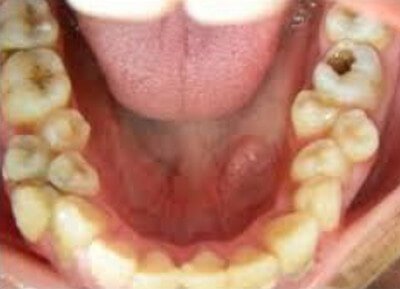

Picture 3: Supernumerary teeth on the lower jaw.